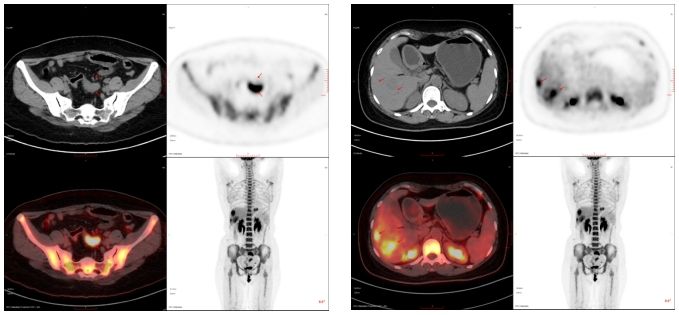

40歲,女,外院查腫瘤標志物示:癌胚抗原(CEA)411.00 ng/ml,糖類抗原19-9(CA19-9)30.0 U/ml;來我科行PET/CT檢查。

PET/CT診斷:乙狀結腸癌伴肝臟、淋巴結多發轉移;隨后病理確診為乙狀結腸腺癌。